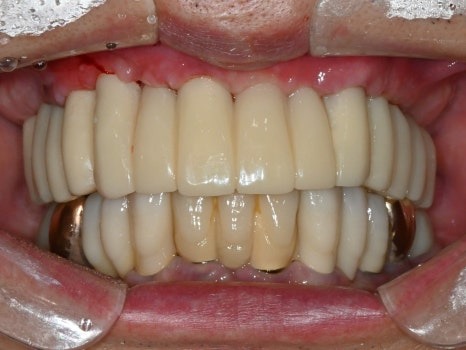

서울하늘에치과의 디지털 임시치아

좋은 계획과 기술로 만들어진 임시치아는

불과 몇 시간만에 환자분의 생활을

극적으로 달라지게 할 뿐만 아니라

환자와 의료진의 신뢰 관계를 증진시켜서

향후 치료 과정을 수월하게,

결과를 훌륭하게 만들 수 있습니다.